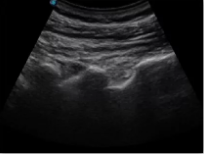

不同的探頭對應(yīng)于不同的臨床領(lǐng)域,不同的探頭頻率也應(yīng)用于不同的人體組織。超聲波在人體中的衰減與探頭頻率有關(guān),探頭頻率越高,穿透力越弱,分辨率越高,而探頭頻率越低,穿透力越強,分辨率越低。因此在檢查淺表器官時應(yīng)選用高頻探頭,而檢查深部臟器時則選用穿透性強的低頻探頭。